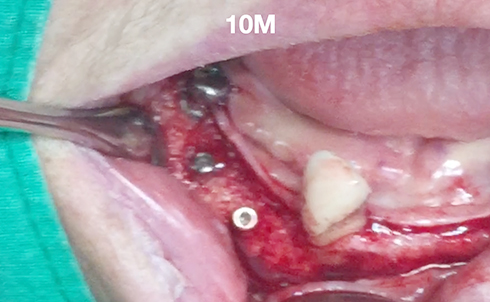

Implants/Bone Grafting

Partial edentulous clinical cases